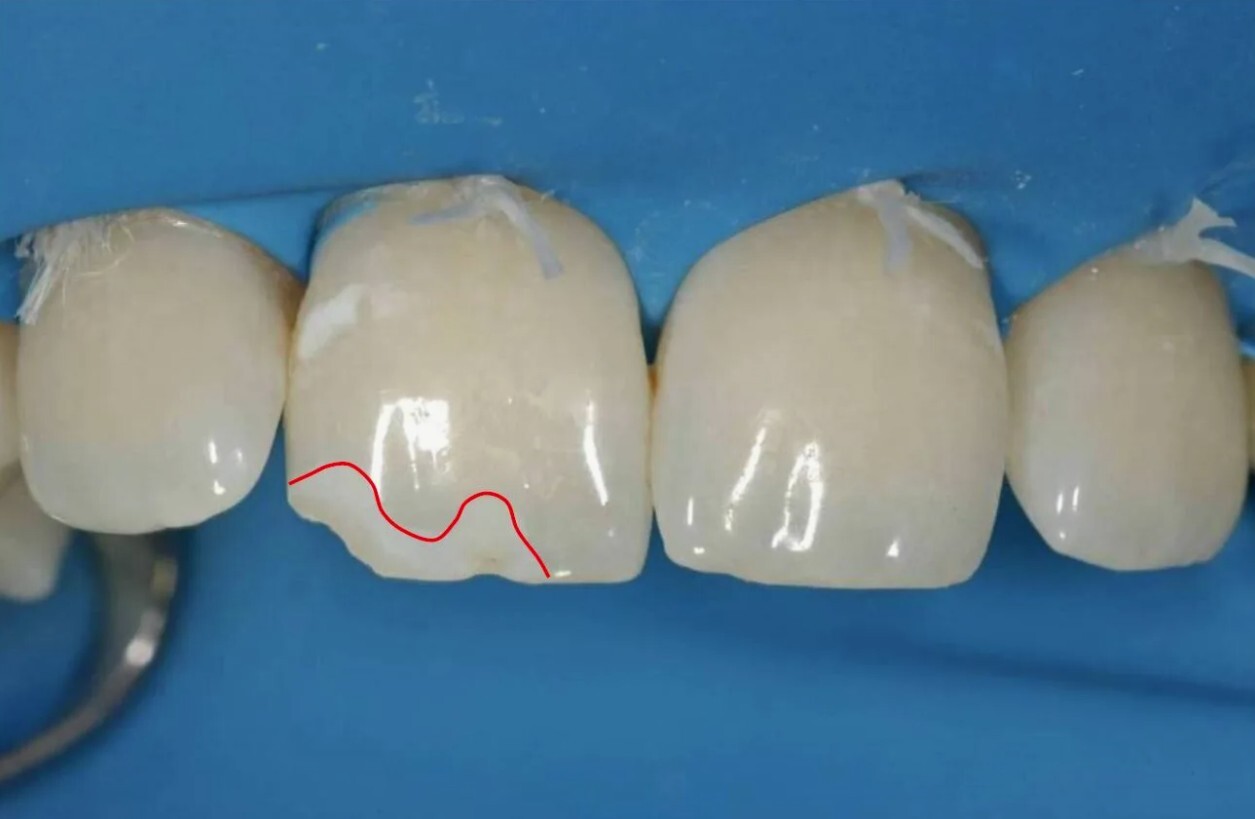

Сколы эмали — одна из частых проблем, с которой пациенты обращаются в стоматологические клиники. Они возникают из-за травм, неправильного прикуса, чрезмерной нагрузки или кариеса. Такие дефекты могут быть не только эстетической проблемой, но и источником повышенной чувствительности зубов и риска дальнейшего разрушения.

Композитные реставрации — самый распространённый метод. С помощью современных композитных материалов стоматолог восстанавливает форму и цвет зуба, добиваясь высокой эстетики.